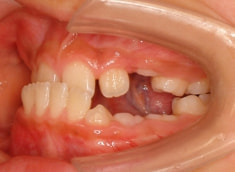

治療開始後3ヶ月で、すでに前歯がジャンプしていますが、ここで注意が必要です。これは前歯の傾斜で反対咬合が一時的に解消しているだけです。ここからしっかりとフェイスマスクを使用し、上顎の牽引をしなくてはいけません。

ジャンプしただけでは「治った」ことにはなりません。今後身長と一緒に伸びてくる下顎の成長に備える必要があります。

治療開始時

治療開始から約3ヶ月後